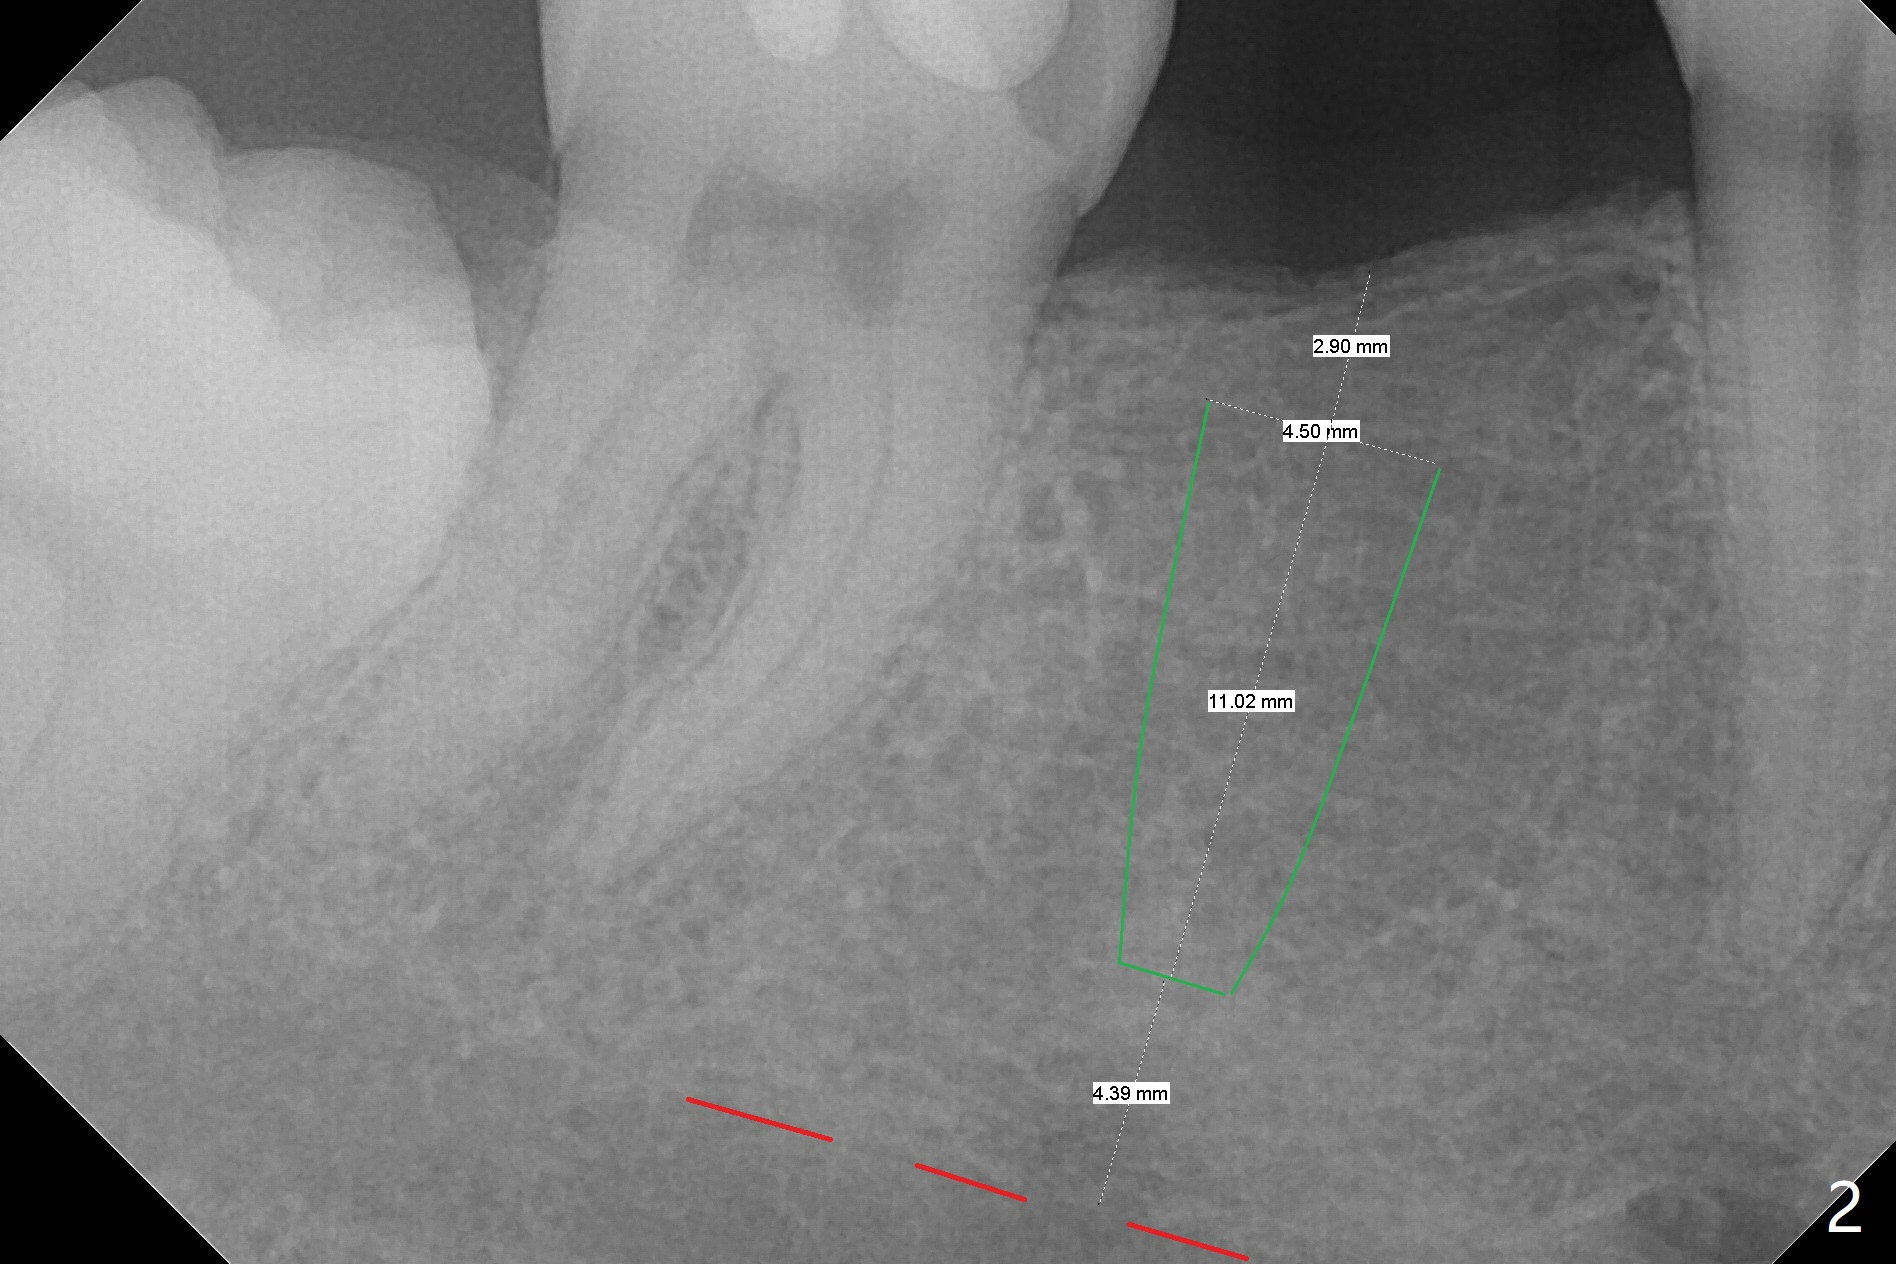

54岁男缺失右下6大约20-30年,但是右上6却没有过度萌出,因为右下7好像近中移位(图一:箭头)。3年前在没有CT检查下,根尖片设计表示植体直径可以4.5毫米(图二)。尽管现在CT检查表明骨头颊舌侧宽度允许5毫米植体(图三),4.5毫米植体(缺牙区近远中间隙小)可以让植体颊侧,舌侧骨板接近2毫米,加上导板应用,以及足够角化龈(临床检查显示),延长植体寿命是比较现实的事情。